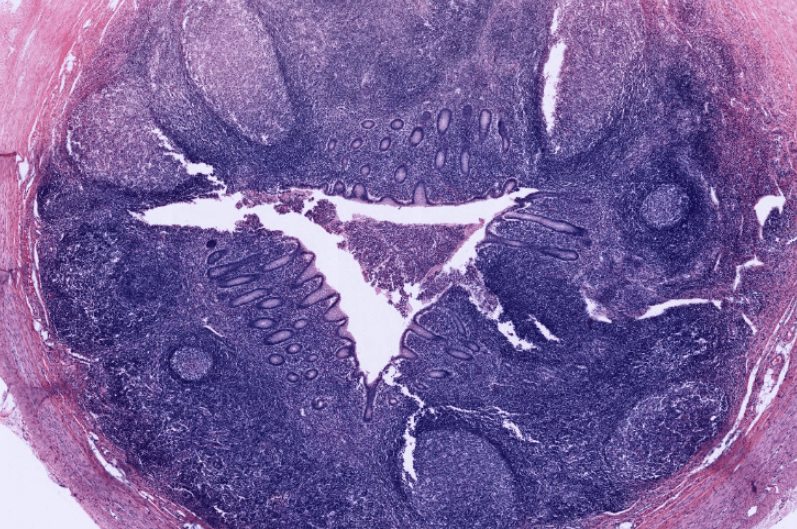

TIMO

Órgano linfoide 1° (primario)

Se compone de una cápsula de TC, una corteza basófila y una médula.

NO hay nódulos linfáticos.

En la médula es posible observar los Corpúsculos de Hassal formados por las células reticuloepiteliales de tipo VI.

El timo es un órgano encapsulado organizado en lóbulosEl timo es un órgano linfoide que carece de nódulos linfáticos y se encarga de la maduración de los linfocitos T.Observe la cápsula de tejido conjuntivo denso irregular que rodea este órgano linfoideEs posible observar gránulos de queratohialina en los corpúsculos de Hassall.La corteza tímica es altamente basófila y encontramos células reticulares epiteliales de tipo I, II, y IIILa médula del timo es fácil de identificar por la presencia de corpúsculos de HasallTimo, HyE.Los corpúsculos de Hassall secretan citocina hematopoyética para ayudar a la maduración de los LTEn la médula tímica es posible observar los Corpúsculos de Hassal formados por las células reticuloepiteliales de tipo VI.Observe la organización del timo, este carece de nódulos linfoides. Timo, HyE.Identifique los septos conjuntivos que organizan el lobulillos al timo.Identifique la basofilia de la corteza en comparación con la médula.En la adolescencia este órgano involuciona a tejido adiposo.Timo adulto, HyE.